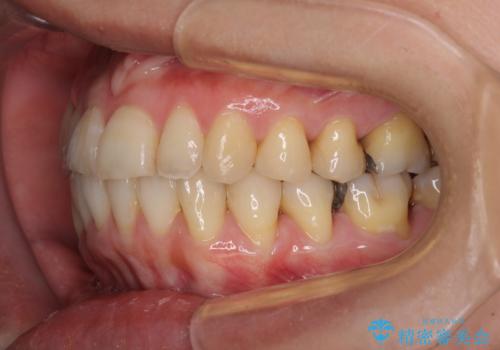

切端咬合をインビザライン矯正で解消

- 前歯のデコボコを気にして来院された患者様です。

上下前歯の先端同士が接触する切端咬合であったため、上顎は歯列を拡大し、下顎はIPR(歯と歯の間を削る)により叢生を解消しながら歯列を小さくすることとしました。

治療途中に前歯に歯髄充血を思わせる痛みが認められたため、無理のない歯の移動と頻繁な経過観察を行いました。

切端咬合はスムーズに解消され、前歯の負担を軽減させることができました。